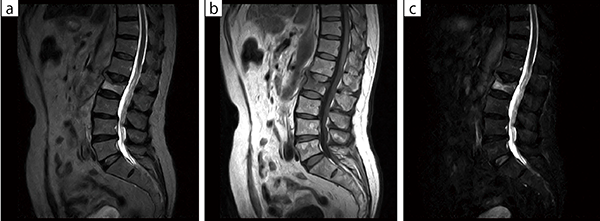

■症例1:脊椎圧迫骨折

骨折では骨内部に出血するため,T2強調画像で高信号を示す。経過とともに信号は低下するが,本症例ではT2強調画像(a)と脂肪抑制画像(c)で第2腰椎に高信号が認められ,新鮮骨折と診断できる。

a:T2WI,SAG,FOV:300mm,TR/TE=5916/125,スライス厚:5mm

b:T1WI,SAG,FOV:300mm,TR/TE=755/25,スライス厚:5mm

c:STIR,SAG,FOV:300mm,TR/TE/TI=6081/96/110,スライス厚:5mm